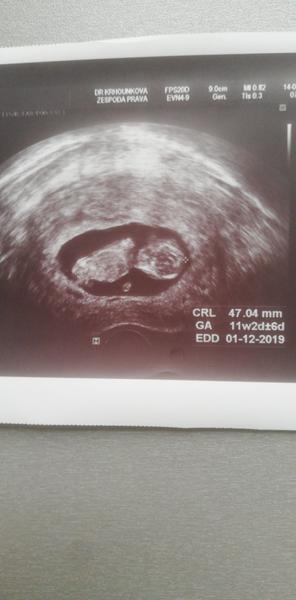

Tady asi taky nikdo nepozná co

Ahoj holky vkládám asi uz na 3 skupinku, čím víc tim líp 😄😄co u mě má někdo ponětí,? doktorka říká chlapeček, pindika jsem označila nůžkami ❤️😄dekuji a hezky den